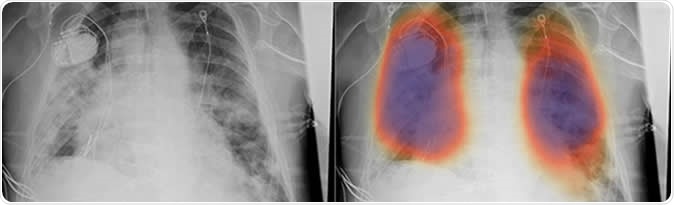

Chest X-rays from a patient with COVID-19 pneumonia, original x-ray (left) and AI-for-pneumonia result (right). Patient has a pacemaker device and an enlarged heart, which indicates that the AI algorithm is powerful enough to work even when the patient has underlying health issues.

The new algorithm overlays X-rays with color-coded maps to detect pneumonia. It has been trained with about 22,000 notations by human radiologists. To test their algorithm, the team used the artificial intelligence approach to ten chest X-rays from five patients in China and the United States with COVID-19. The ten images were published in medical journals.

Even if the images were taken at different hospitals, the algorithm was able to detect localized areas of pneumonia consistently. Published in the Journal of Thoracic Imaging, the results show that the new method can detect pneumonia in patients rapidly, providing prompt treatment.